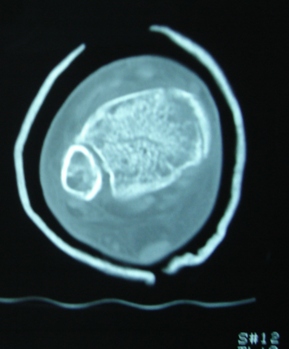

Продолжая тему представляю данные КТ нашей пациентки.

Имя     : Скан 14.JPG

Тип     : image/jpeg

Размер  : 45081 байтов

Url     : http://weborto.net:8080/pipermail/ortho/attachments/20091107/a87a6ebe/attachment-0004.jpeg